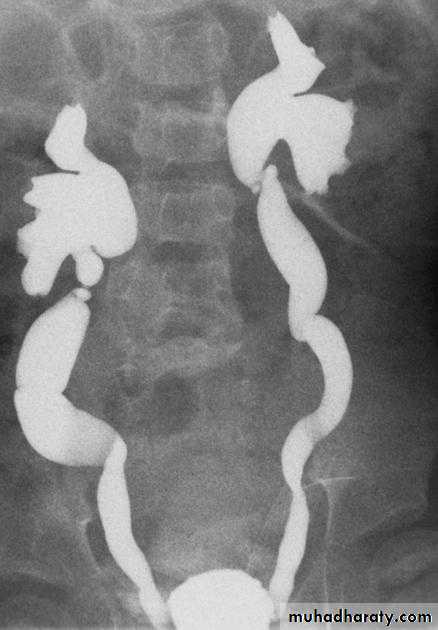

Normal IVU series

Uretrocele (cobra head shape)distal both sided ureteric ends with dilated both ureters

Uretrocele